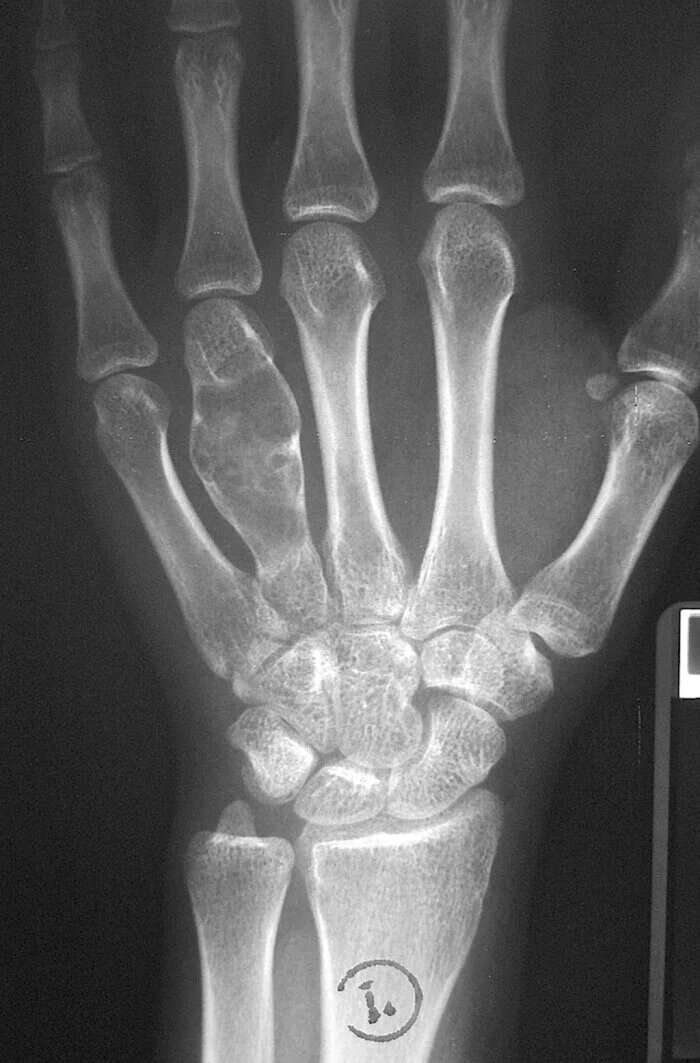

При крупных поражениях зона просветления окружена эндостальным склерозом с истончением и вздутием коры, при этом компьютерная томография позволяет оценить целостность кортикального слоя. Кальцификация в поражении варьирует от точечных до кольцевидных. При локализации в фалангах, энхондромы характеризуются экспансивным литическим ростом. При других локализациях проявляются экспансивным ростом с характерной картиной в виде колец или арок за счет кальцинатов. Типичные энхондромы представляет собой небольшое 1-2 см литическое поражение  без признаков агрессивности:

• узкая переходная зона

• четкие фестончатые границы

• может встречаться вздутие кортикального слоя, но без патологического перелома целостность его не должна прерываться

• могут визуализироваться кальцинаты: признак колец и арок

• отсутствует периостальная реакция

• отсутствует мягкотканный компонент

КТ призывника с диагнозом энхондрома проксимальной фаланги третьего пальца правой стопы.